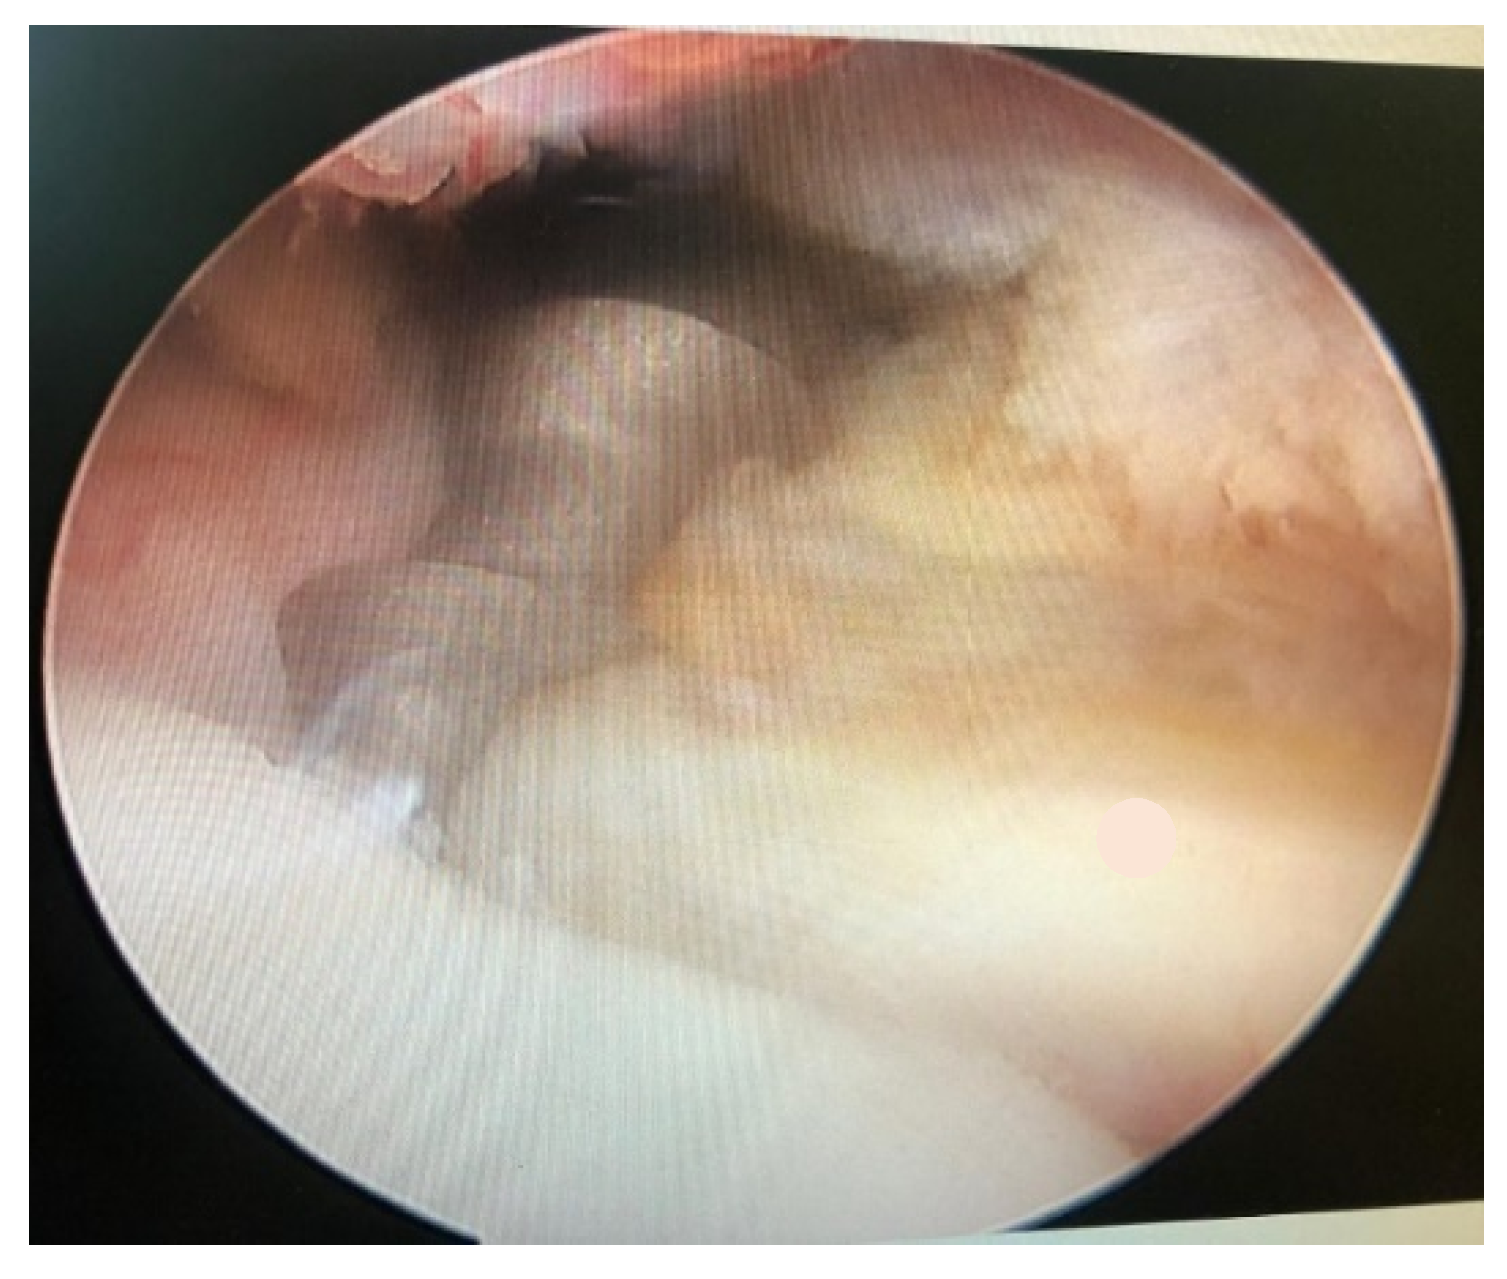

Posterior Shoulder Dislocation with Engaging Reverse Hill–Sachs Lesion: A Retrospective Study of Ten Patients Treated with Arthroscopy or Open Reduction and Stabilization

3. Results